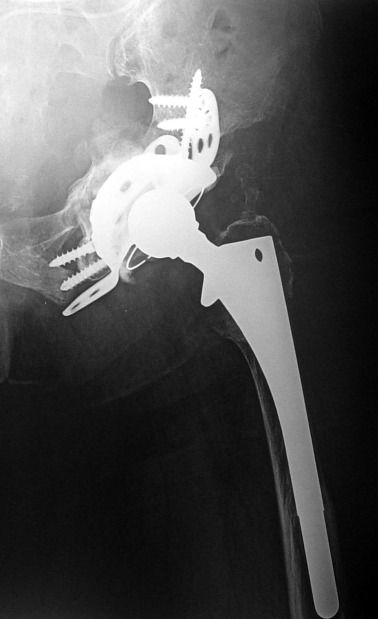

78 year-old female patient referred to the emergency department with left-sided upper abdominal pain. Blood chemistry was normal. Physical examination revealed a mass lesion in the suprapubic area which was initially considered as a distended bladder. Emergency abdominal ultrasound examination demonstrated grade 3 hydronephrosis in the left kidney and a dilated ureter, together with a cystic mass in the pelvis. The mass compressed the bladder and contained multiple echogenic foci within a thin-walled cyst, but no solid components or septae were visible. For further characterization of the mass, an abdominal CT examination with IV contrast material was performed (Fig. 1 ). Grade 3 hydronephrosis of the left kidney and dilation of the ureter into the pelvis was evident. A large cystic mass of 8 cm in diameter was located in the left hemipelvis, compressing the bladder anterolaterally to the right, separating the bladder and the rectum. Containing heterogeneous material, the mass appeared hypodense without any contrast enhancement either in the wall or within. The mass seemed to be adjacent to the left posterolateral pelvic side wall, where streak artefacts emanating from a total hip arthroplasty caused deterioration of the images. No other pathology could be identified.

Abdominal CT. A large hypointense mass displaces the bladder and the rectum, ...

Abdominal CT. A large hypointense mass displaces the bladder and the rectum, filling rectovaginal space. Close contact between the mass and acetabulum, with a beak-like extension towards the acetabular screws, is evident. Osteolysis of acetabulum is prominent.